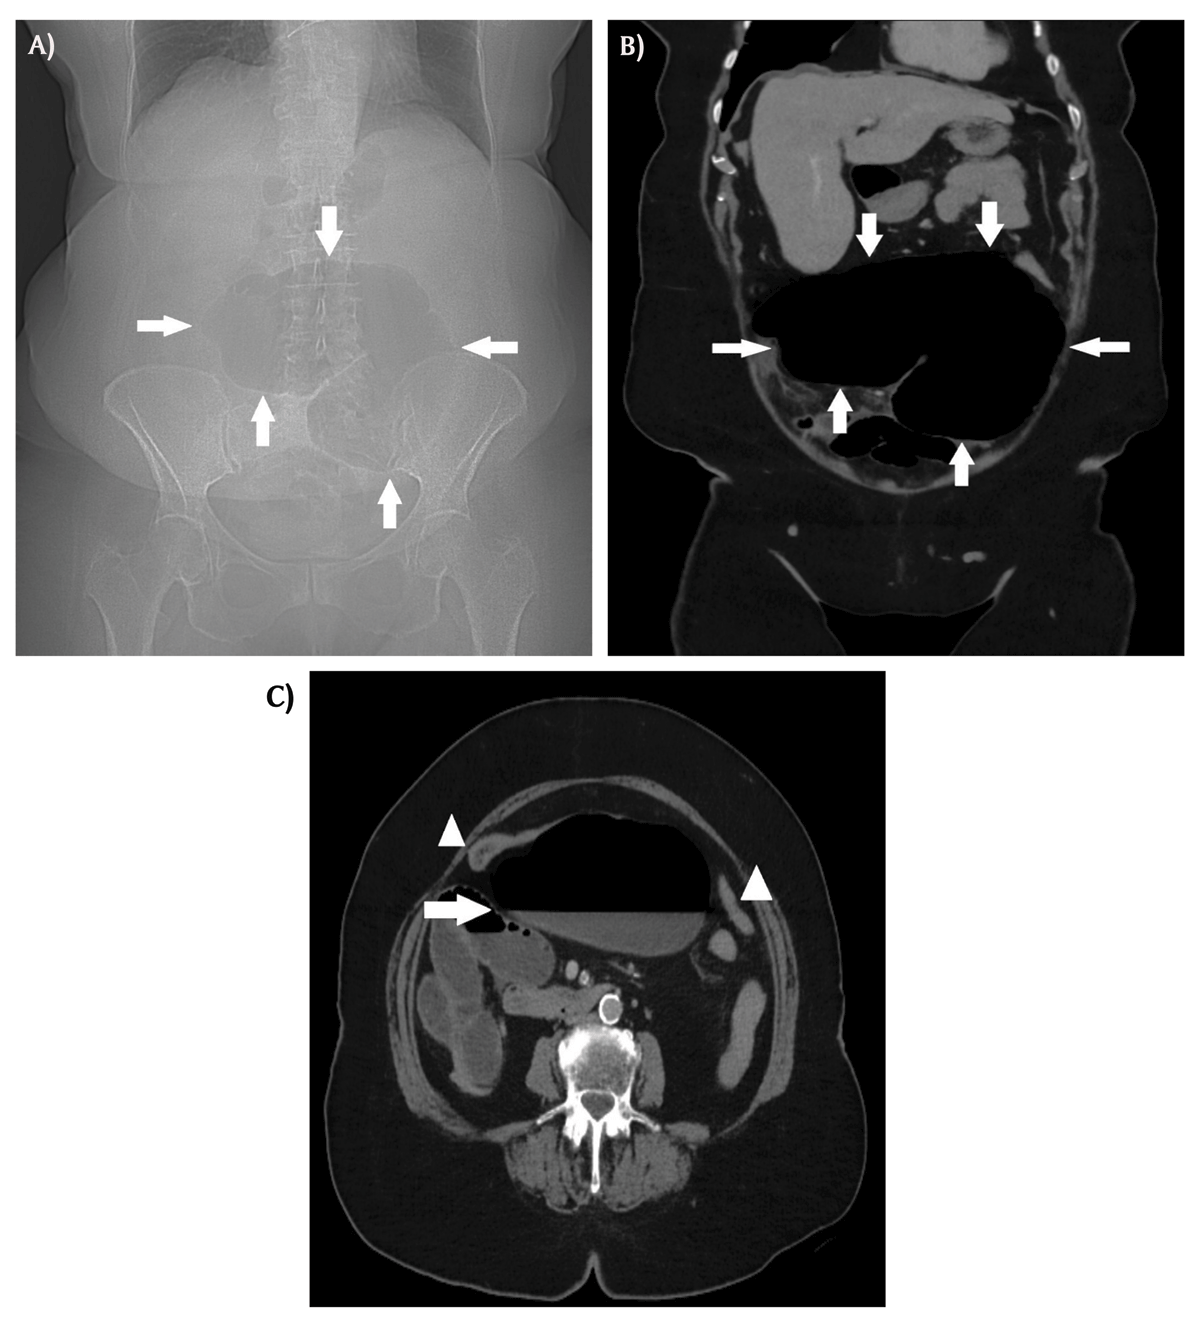

Scout view of abdominal computed tomography (CT) showed an air-distended bowel loop in the lower abdomen with the shape of a coffee bean (Figure 1A, arrows). Coronal contrast-enhanced CT showed a distended cecum measuring 9 centimeters (Figure 1B, arrows), with air-fluid level (Figure 1C, arrow) and collapse of the transverse and left colon on axial images (Figure 1C, arrowheads). The coronal images also showed a clockwise whirl of spiraling collapsed cecum; fatty mesentery with enhancing engorged vessels and a central soft-tissue density was noted (Supplementary video). On sagittal reformatted images, gradual tapering of the wall of the obstructed cecum at the site of the whirl resulted in a stenosis with the appearance of a bird’s beak (Figure 2). The distal ileum was fluid-filled. There were no signs of bowel perforation. The presumed diagnosis of closed loop obstruction due to cecal volvulus was confirmed by laparoscopy. Right hemicolectomy was performed.

Figure 1

Abdominal CT is crucial to make a correct diagnosis. Torsion of the cecum may rotate clockwise or counterclockwise in the axial plane around its long axis. If present, the obstructed cecum will appear in the right lower quadrant. An extreme air-distended cecum with visible haustral folds may resemble a coffee bean on scout view, axial, or coronal CT images. A whirl sign presents a centrally located twisted cecum surrounded by swirling mesenteric vessels and fat. A central soft-tissue density pinpoints the source of the twist. A bird’s beak sign results from gradual tapering of the cecum at the site of torsion, resulting in the appearance of a bird’s beak [1].